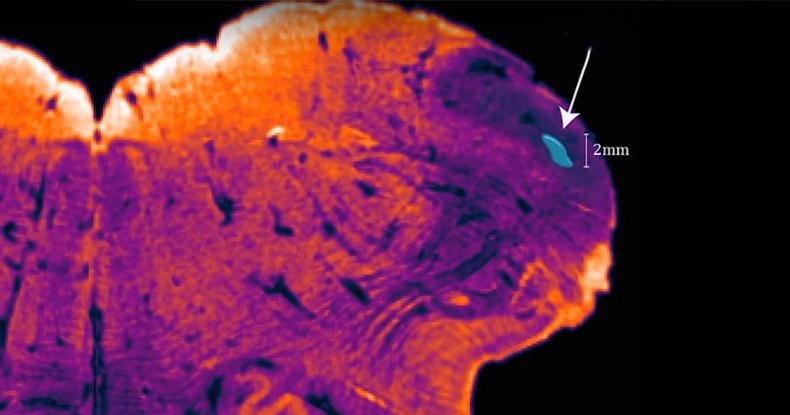

Новый участок обнаружила группа исследователей из Австралии во главе с нейробиологом Джорджом Паксиносом (George Paxinos). Данный участок решили назвать endorestiform nucleus, так как он расположен внутри нижней мозжечковой ножки (inferior cerebellar peduncle). Он находится у основания — рядом с областью, где уже начинается спинной

Паксинос с другими исследователями смог подтвердить существование endorestiform nucleus, используя относительно новый метод, разработанный для получения более четких изображений мозговых тканей. Данная техника позволяет отслеживать в

Расположение endorestiform nucleus наводит Паскиноса на мысль, что данная область задействована в мелкой моторике. У других приматов этот участок пока не был обнаружен, и возможно, endorestiform nucleus является очередной уникальной чертой человеческой нервной системы. Пока, впрочем, это утверждать рано: проверить идею Паскинос рассчитывает в будущих исследованиях